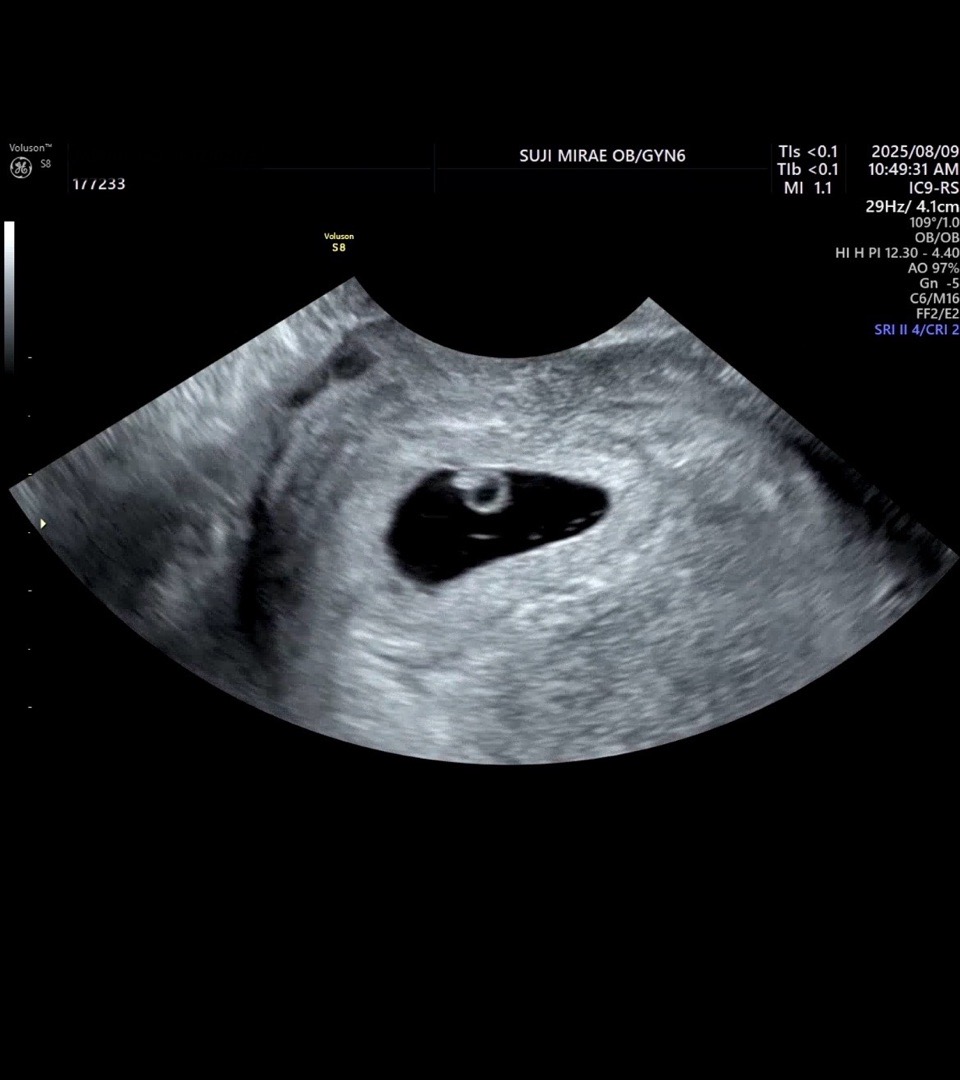

6주0일 반지랑 심장소리 듣고왔어요!

저번주 주말 초음파했을때엔 아직 너무 작아서 오늘 심장소리까지 들을줄은 몰랐는데, 듣자마자 누워서 울뻔했어욬ㅋㅋㅋㅋ 눈물 참느라 혼났네요... 기분이 너무너무 이상하더라구요ㅠㅠ 일주일만에 이렇게 심장을 만들어내서 반짝이고있다니 정말 신기해요... 이제 슬슬 입덧 시작인가봐요.. 묘하게 메스껍고 하루종일 체한 느낌이에요. 조금만 먹어도 배부르고 소화도 안돼고 ㅠㅠ 임신 초기 힘드네요. 날도 더운데 다들 힘내자구요🥹

112bpm이요~